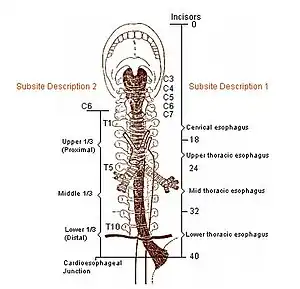

Structure

The esophagus is one of the upper parts of the digestive system. There are taste buds on its upper part.[3] It begins at the back of the mouth, passing downward through the rear part of the mediastinum, through the diaphragm, and into the stomach. In humans, the esophagus generally starts around the level of the sixth cervical vertebra behind the cricoid cartilage of the trachea, enters the diaphragm at about the level of the tenth thoracic vertebra, and ends at the cardia of the stomach, at the level of the eleventh thoracic vertebra.[4] The esophagus is usually about 25 cm (10 in) in length.[5]